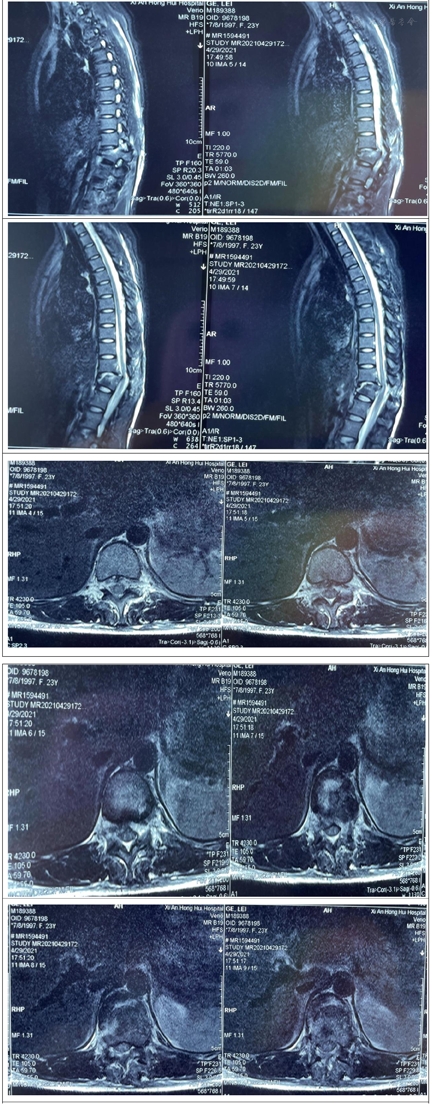

胸椎CT示:胸12椎体骨折伴脱位,相应水平椎管内骨块占位,伴局部后凸畸形。胸椎MRI示:胸12椎体骨折脱位,相应水平硬膜囊及脊髓受压,并脊髓损伤。

西医诊断依据:(1)主诉:坠落伤致双下肢感觉功能障碍1周余。(2)专科检查:抬入病房,被动体位。腰背部可见原手术切口,愈合良好,未见明显红肿及渗出。感觉系统:双下肢感觉大致正常,肛周感觉减退。双下肢体关节位置觉、运动觉存在。运动系统:双侧肢体未见肌肉萎缩。双侧肢体肌张力不高。肌力:左侧:髂腰肌肌力Ⅲ级,股四头肌肌力Ⅲ-级,胫前肌肌力Ⅲ-级,足拇背伸肌肌力级Ⅲ-,趾屈肌肌力Ⅲ-级;右侧:髂腰肌肌力Ⅲ级,股四头肌肌力Ⅲ级,胫前肌肌力Ⅲ级,足拇背伸肌肌力级Ⅲ,趾屈肌肌力Ⅲ级;浅反射:上、中、下腹壁反射正常,肛门反射减弱。深反射:双侧膝腱反射、跟腱反射减弱。病理征:双侧Hoffman征(-),Rossolimo征(-),Babinski征(-),双侧髌阵挛、踝阵挛(-)。骶残留:肛周针刺觉减弱,肛门深压觉减弱,肛门括约肌松弛,自主收缩存在。不可以独自坐立,不能独自站立。洗漱、穿衣、进食等ADL完全依赖。(3)辅助检查:胸腰椎CT(2021年4月29日外院)胸12椎体骨折伴脱位,相应水平椎管内骨块占位,伴局部后凸畸形。胸椎、腰椎、颈椎MRI提示:①胸12椎体骨折脱位,相应水平硬膜囊及脊髓受压,并脊髓损伤;②腰3椎体骨折,胸12附件区软组织肿胀,结合西安市红会医院CT检查胸12附件骨折;③腰5-骶1椎间盘变性、突出,同水平硬膜囊受压;④胸腰骶部软组织水肿;⑤颈椎生理曲度变直,颈3~4、颈4~5、颈5~6椎间盘变性、突出,相应水平硬膜囊受压。